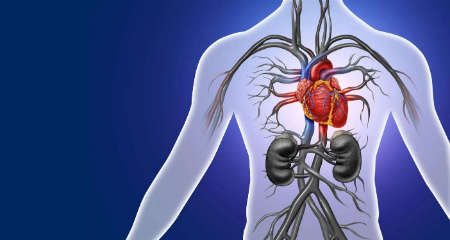

بزرگشدگی دهلیز چپ چیست؟

بزرگشدگی دهلیز چپ زمانی رخ میدهد که یکی از حفرههای قلب شما بزرگتر از حد طبیعی شود. این اتفاق به مرور زمان رخ میدهد وقتی دهلیز چپ شما سعی میکند با مشکلاتی مانند فشار خون بالا در بقیه قلب سازگار شود.

گاهی ممکن است مشکلی در بطن چپ شما وجود داشته باشد که خون را به آئورت پمپ میکند. برخی افراد هم مشکلی در دریچه میترال دارند که اجازه میدهد خون بین دهلیز چپ و بطن چپ حرکت کند. این مسائل میتوانند فشار بالا و/یا حجم زیاد خون در دهلیز چپ ایجاد کنند.

دهلیز چپ شما میتواند بزرگتر شود و کش بیاید وقتی سعی میکند با این فشار بالا و/یا حجم زیاد سازگار شود. این کشیدگی باعث زخم و آسیب به دهلیز شما میشود. مثل برادر بزرگتری است که سعی میکند به خواهر و برادرهایش کمک کند بار را حمل کنند اما خودش آسیب میبیند.